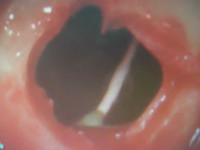

この症例は左上6番部に鈍痛があるとのことで来院された患者様でした。

CTにて精査させて頂きました所6番の遠心頬側根、根尖より根充用のポイントが押し出されてきており、上顎洞内に大きく突出しておりました、これが上顎洞炎併発の原因であると考え、頬側より小さく骨窓を開窓しまして、ポイントを除去し、同時にこれもまた上顎洞内に突出している歯根の尖端を切除しオペ終了といたしました。